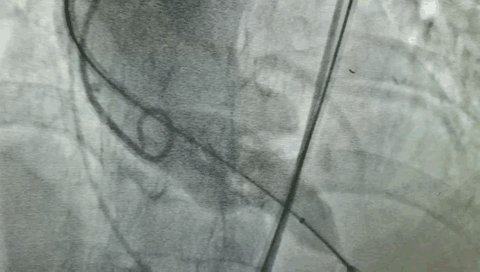

术前就和周玉杰教授团队做了周密研讨和细致评估,包括体外模拟植入瓣膜后的冠脉情况。术中,也做了多种应急预案,一方面备了体外循环机器,万一不行,就转机上体外循环支持;另一方面,在左冠主干的位置放了导丝,如果造成左冠动脉缺血,会立即行冠状动脉球囊扩张➕支架植入治疗。

在瓣膜的选择上,也充分考虑到冠脉开口位置低、主动瓣左冠的窦部比较小的问题,最终采用16mm球囊预扩,20mm瓣膜释放,一个半小时左右的手术过程顺利,冠状动脉开口没有受到影响,冠脉的供血也比较好。